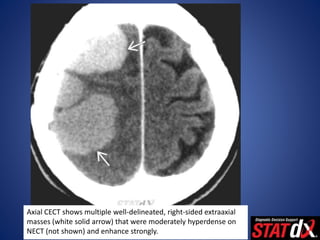

Axial CECT shows multiple well-delineated, right-sided extraaxial

masses (white solid arrow) that were moderately hyperdense on

NECT (not shown) and enhance strongly.

Axial CECT showsmultiple well-delineated, right-sided extraaxial masses (white solid arrow) that were moderately hyperdense on NECT (not shown) and enhance strongly.